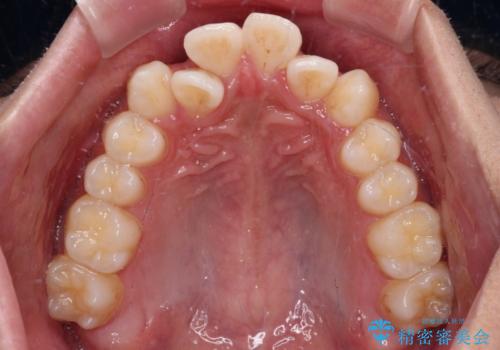

- 八重歯と口元の閉じにくさを気にして来院された患者様です。

非抜歯矯正で歯列を整えると、治療後に口元が今よりも突出する可能性が高かったため、上下左右の第一小臼歯4本を抜歯し、ワイヤー装置にて矯正治療を行うこととしました。

患者様の望んでいた通りの歯列や口元に仕上げることができました。